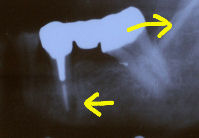

右下6番虫歯になりました。

右下6番の虫歯がかなり大きくなっていました(一枚目写真)。軟化象牙質を全て取ってしまうと歯髄に達してしまうのでindirect pulp cappingを行いました。一年後には歯髄の側に第二象牙質ができています(二枚目写真)。その後軟化象牙質を完全に取り去りインレーで修復しました(三枚目写真)。6番目の歯は永久歯の中でも一番虫歯になりやすい歯ですが、小学3年生の段階で神経がなくなると一生は持ちません。なるべく神経を残すことができるようにこういった治療もあるのです。